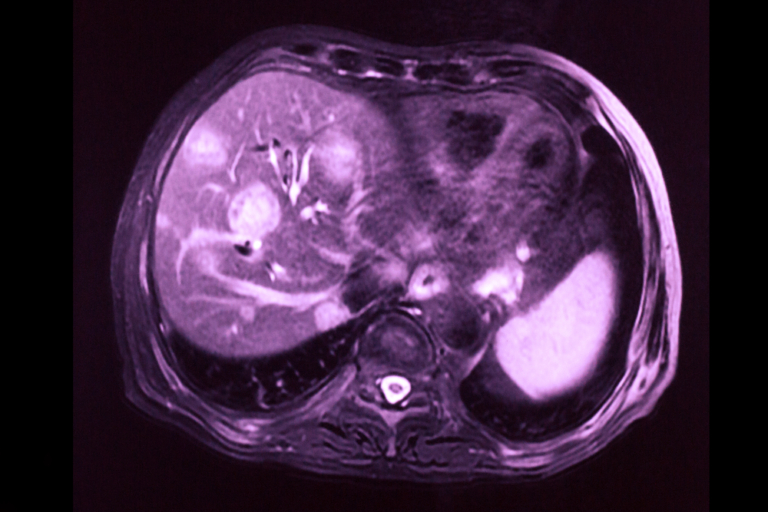

- Rezonanța magnetică nucleară (RMN): RMN-ul poate furniza informații suplimentare despre structura și natura metastazelor hepatice.